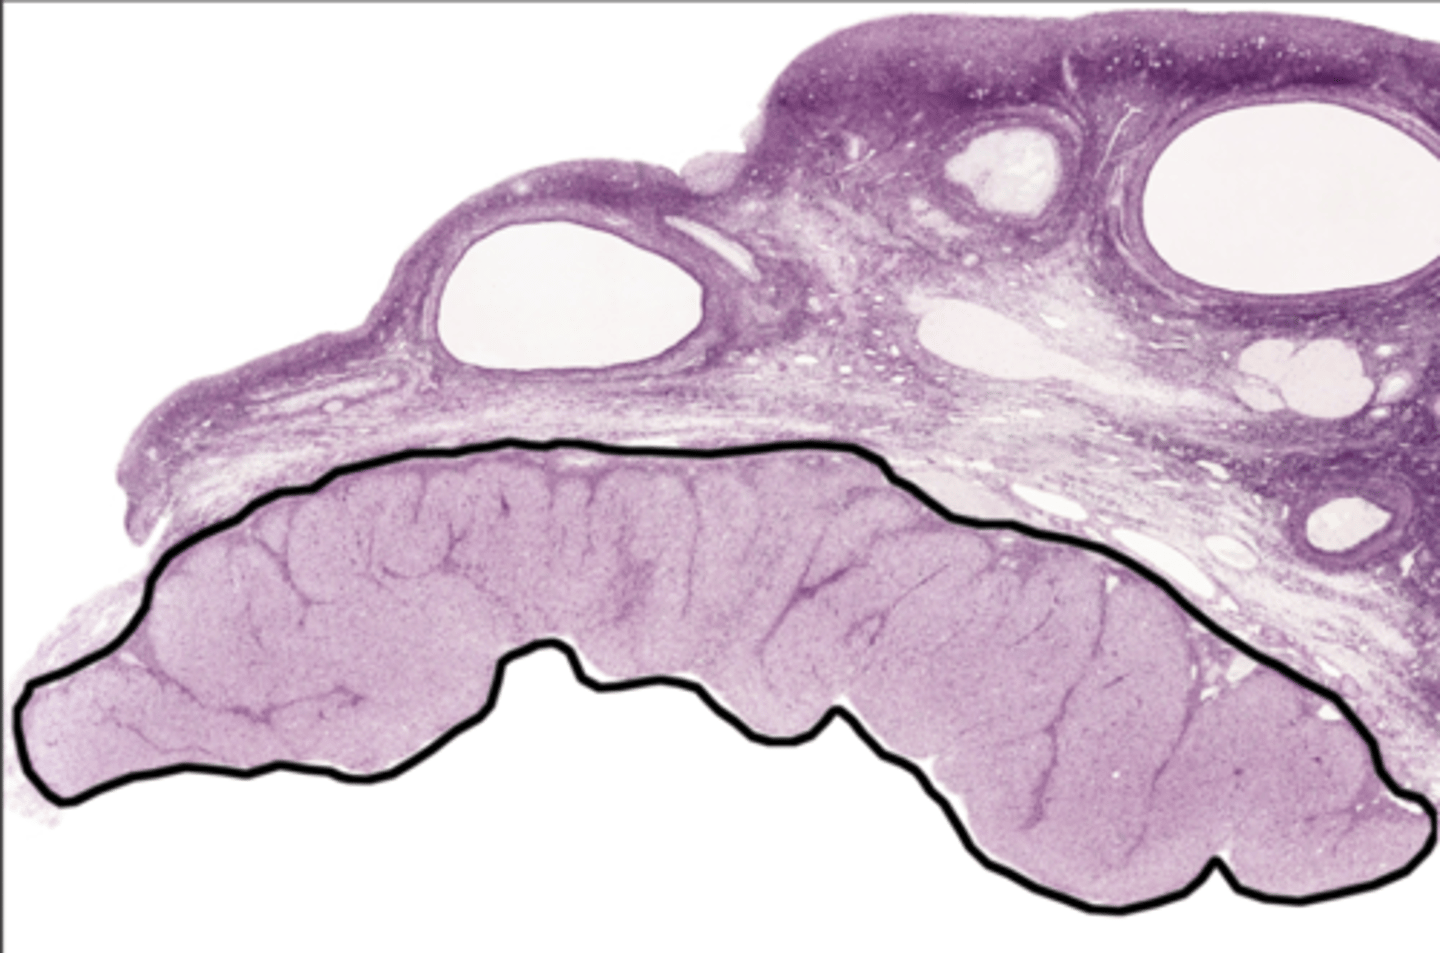

Perimetrium

Perimetrium

Myometrium

Myometrium

Endometrium

Endometrium

proliferate functional layer

secretory functional layer

menstrual functional layer

proliferate basal layer

secretory basal layer

menstrual basal layer

Uterine gland

Fundus

Body of uterus

Cervix

Internal os

Cervical canal

External os